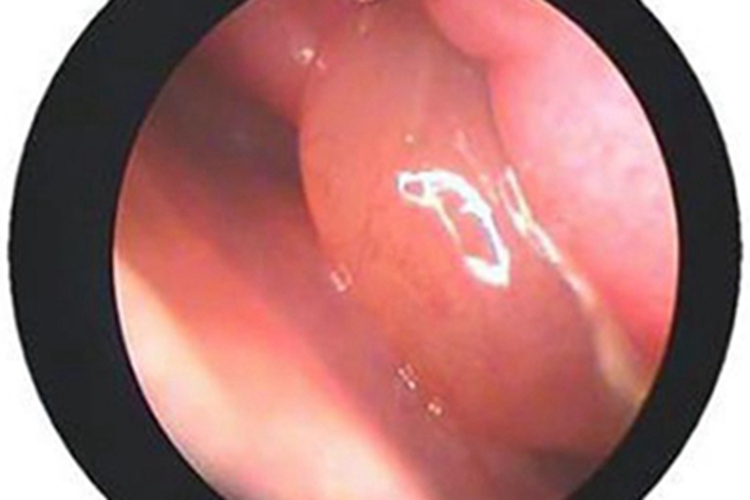

鼻旁窦炎患者在进行鼻内镜检查时,会发现鼻腔内黏膜上有一个肿块,突出鼻黏膜表面,整体呈椭圆形,表面光滑,质地柔软,堵塞部分鼻腔,可能伴有鼻塞、嗅觉减退。